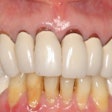

In the second article, the authors cite the case of an 81-year-old who developed a squamous cell carcinoma (SCCa) adjacent to an implant. The woman had a history of oral lichen planus (OLP). She developed an in situ SCCa on the left mandibular ridge, which was edentulous, three years after undergoing implant-supported reconstruction. A year after a marginal mandibular resection, a recurrence developed over the resected area, requiring segmental mandibulectomy (JADA, August 2008, Vol. 139:8, pp. 1061-1065).

As the use of endosseous implants continues to expand, careful follow up after procedures also needs to keep pace, the researchers found. A routine checkup every three months is the goal for an industry standard, keeping in mind that recurrent primary malignancy can masquerade as benign peri-implant complications such as peri-implantitis.